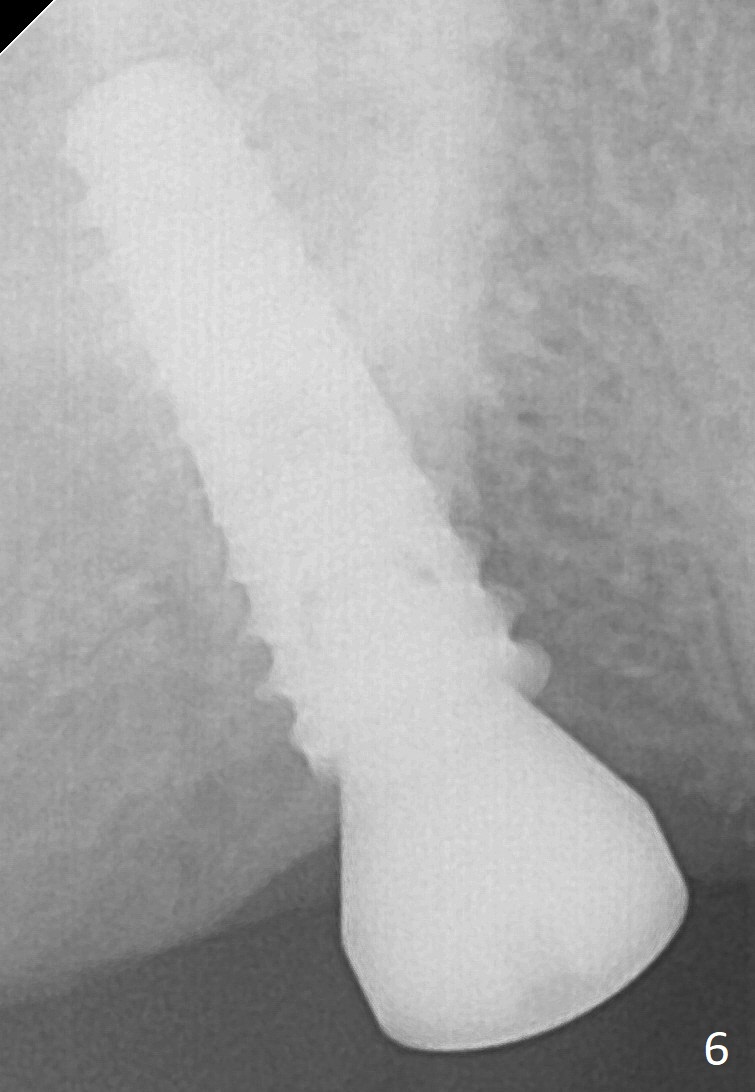

The edentulous ridge at the site of #2 is wide. Magic split is used to gain access, test bone density and start osteotomy for 9 mm (gingival level). A 1.6 mm drill is used to extend the osteotomy for depth of 13 mm. The osteotomy position and trajectory is confirmed with a parallel pin (Fig.1), which is ideal. The remaining osteotomy is finished with Magic Expanders from 3 to 4.3 mm for 15 mm. The trajectory is confirmed again with insertion of a 4.5x11 mm dummy implant at the depth of 15 mm (Fig.2). When a definitive IBS implant (5x13 mm) is placed with insertion torque >45 Ncm, the distal coronal end is not subcrestal (Fig.3-5). As the implant is placed deeper, it started to lose primary stability. When a pair abutment is placed, it keeps turning. Finally a healing abutment (6x3 mm) is placed unstable. In brief, taking several X-ray films help control osteotomy and implant position and trajectory. The implant is unstable 7 months postop (Fig.6). With local anesthesia, the implant is placed deeper by 1 mm with apparent increase in torque and a 6x4 healing abutment placed. The implant is stable 11 months postop. With 5.5x4(4) mm abutment placed, impression is taken. PA and BW will be taken after cementation of the crown. There is no bone loss 9 months post cementation (Fig.7). Return to Upper Molar Immediate Implant, 18-20, 29,30 Xin Wei, DDS, PhD, MS 1st edition 01/09/2017, last revision 08/15/2021